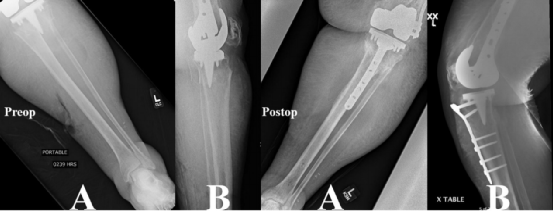

图2. Felix I型骨折术前、术后的正侧位X光片。